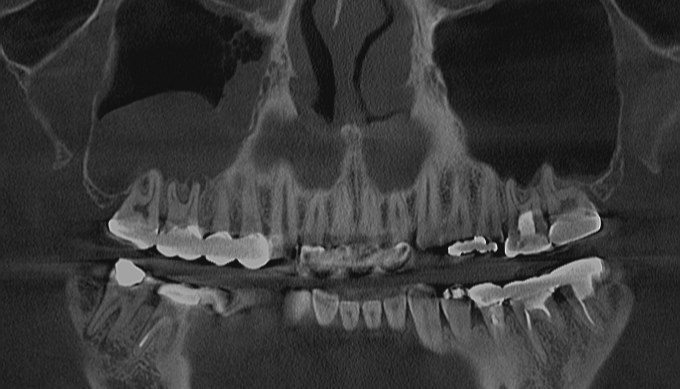

Complications

Immediate placementDong-Seok SohnViews : 3 |

Peri implantitisDong-Seok SohnViews : 2 |

management of sinusitisDong-Seok SohnViews : 1 |

removal of cystDong-Seok SohnViews : 2 |

closure of oroantral commu..Dong-Seok SohnViews : 64 |

Remioval of displaced impl..Dong-Seok SohnViews : 30 |